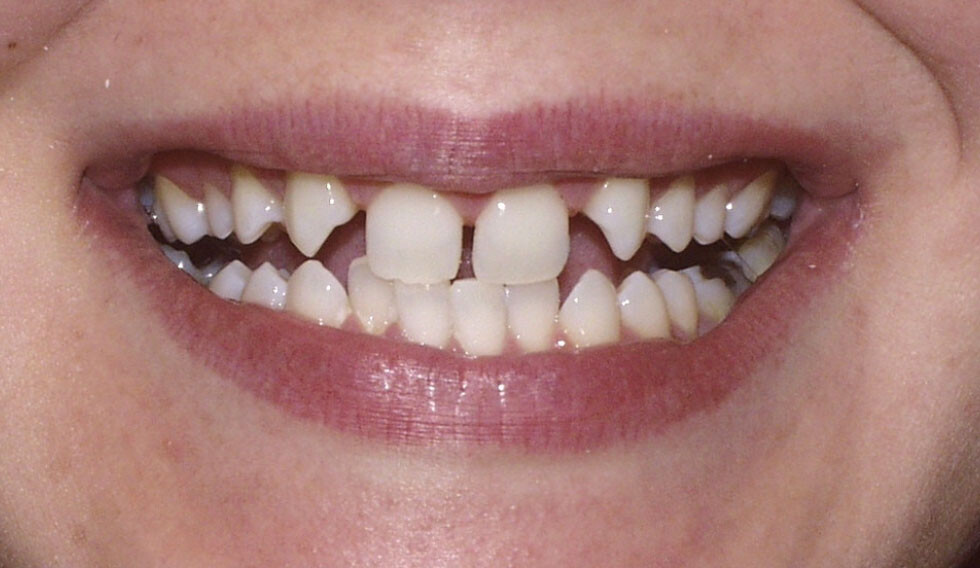

Congenitally missing teeth or hypodontia is a condition where some of the adult teeth do not develop. Although it can also affect the primary teeth, this is quite rare, unless there is an underlying genetic disorder.

Your dental professional will be able to tell if you have any missing teeth. Usually, they will need an x-ray to confirm this. Gaps between your teeth, losing a baby tooth with no adult tooth taking its place or having a baby tooth longer than normal are all signs of having congenitally missing teeth.